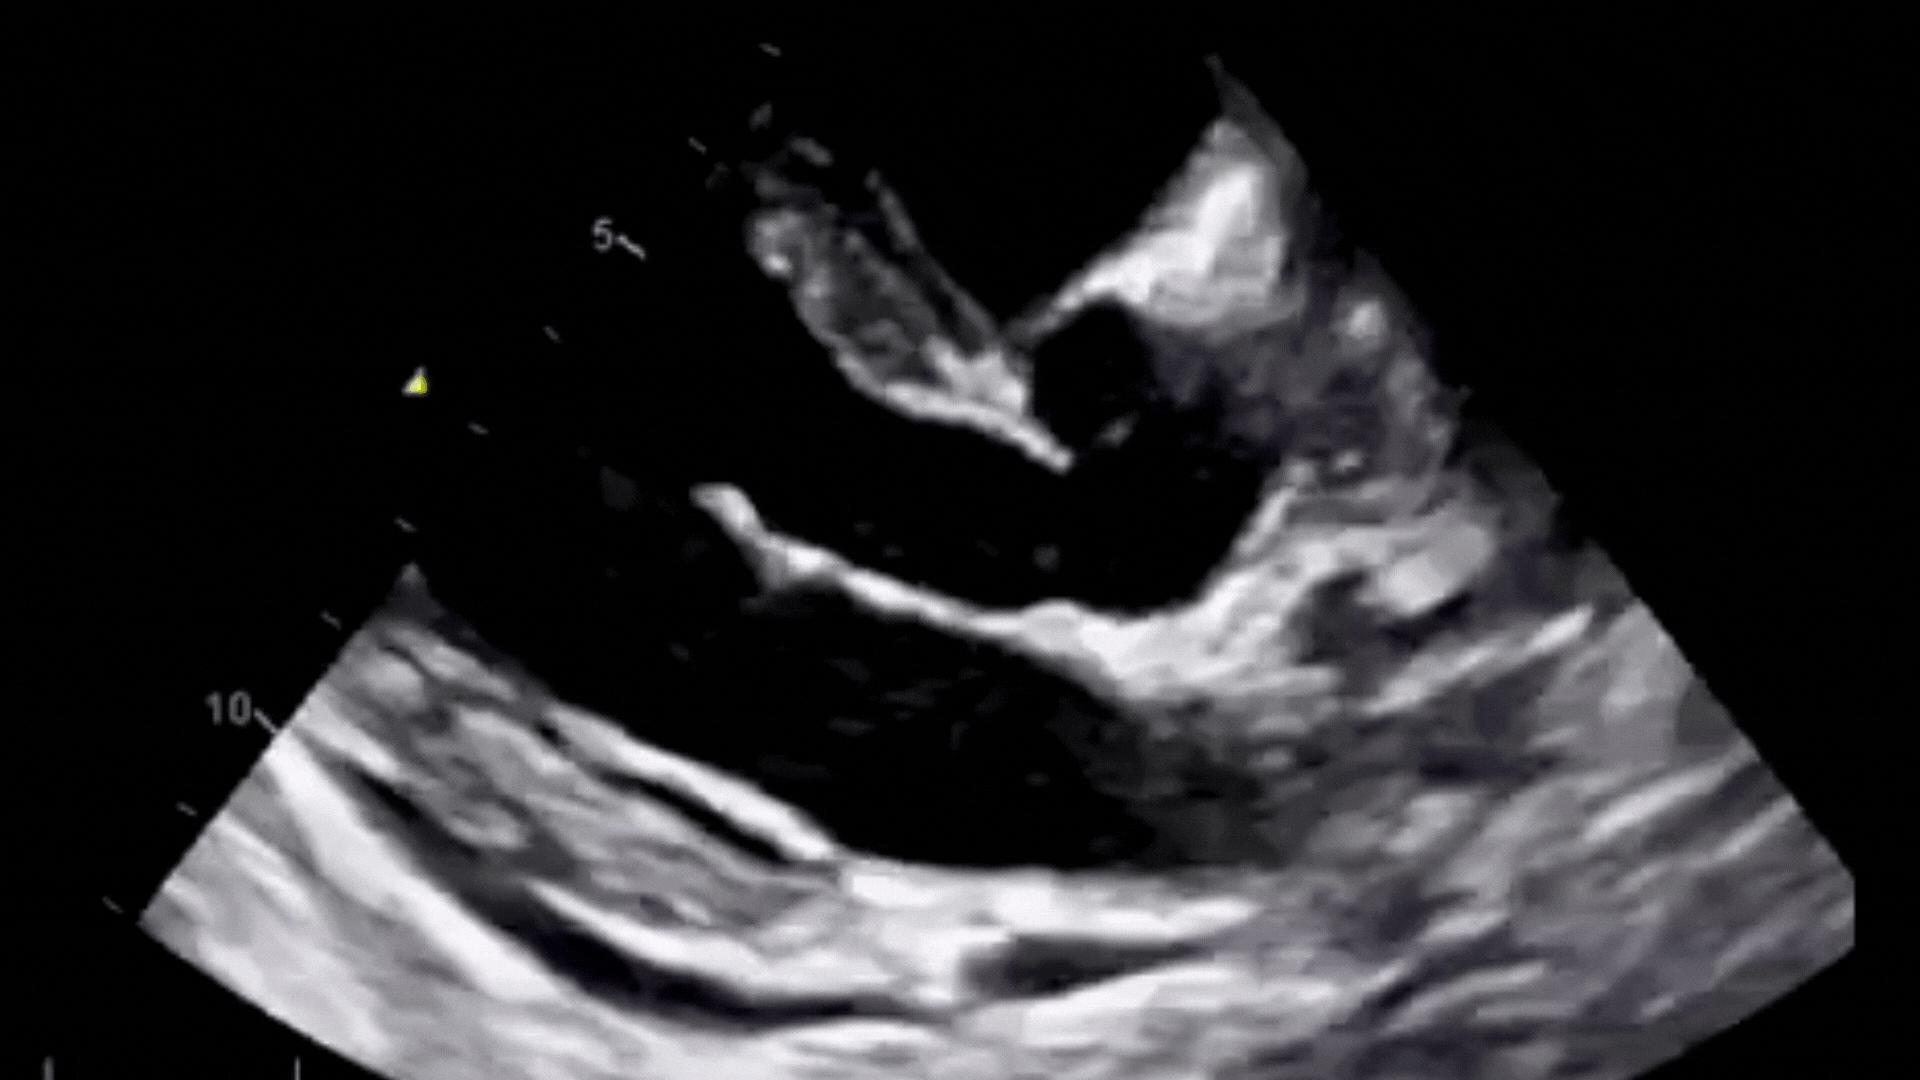

Cette formation immersive de 2 jours à Paris combine enseignement théorique, ateliers pratiques sur échographes et utilisation de modèles de démonstration. Encadré par un deux IPA experts titulaires du DIU d’échographie, ce week-end propose une progression structurée : apprentissage des coupes de référence, maîtrise des mesures fondamentales, analyse hémodynamique et intégration clinique des données.